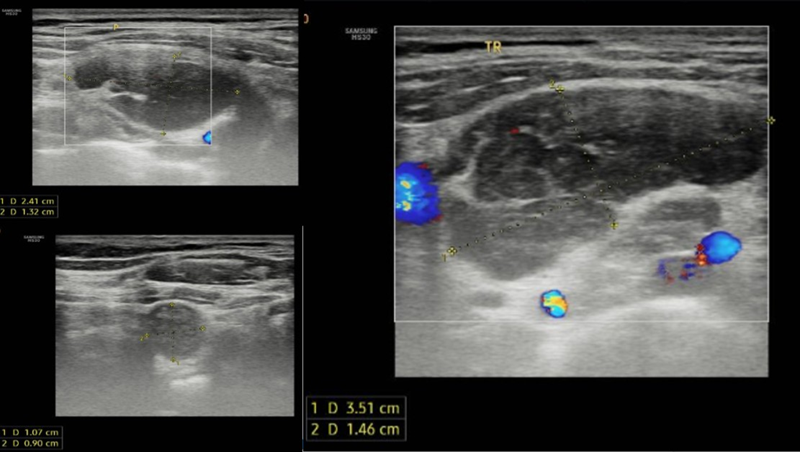

Hình ảnh tổn thương trung thất trên, lan vào rốn phổi trái, ôm quanh và làm hẹp lòng các nhánh động mạch - tĩnh mạch phổi và phế quản thùy trên

CT ghi nhận vùng nền cổ, thượng đòn hai bên có nhiều khối hạch bất thường, bờ đa cung, ngấm thuốc không đồng nhất sau tiêm, hạch lớn kích thước khoảng 32x45mm

Chụp CT toàn thân có tiêm cản quang phát hiện nhiều hạch bất thường vùng nền cổ, hố thượng đòn hai bên và trung thất, các hạch tạo thành đám ôm quanh các mạch máu trong trung thất và ôm quanh phế quản gốc hai bên.